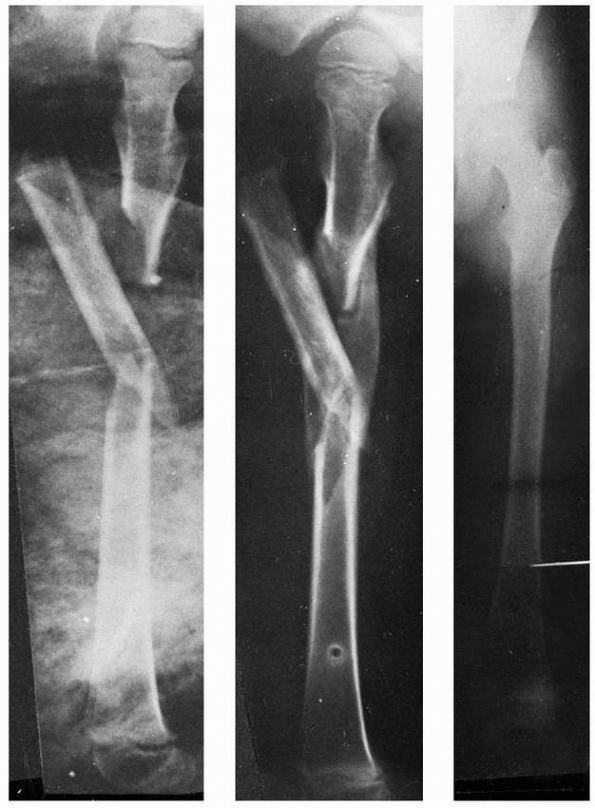

a child between the ages of 5 and 11 years with a length-stable femoral

fracture in the mid-80% of the diaphysis (Fig. 22-16), who has a body weight less than 50 kg.149

Unstable fracture patterns can also be treated with flexible nailing,

but the risk of shortening and angular malunion is greater,185 and supplemental immobilization during the early healing phase may be valuable.

lines that propagate proximally and distally and might be otherwise

unnoticed (Fig. 22-17). Although it is

technically difficult to obtain satisfactory fixation with a retrograde

technique when the fracture is near the distal metaphysis, a 2006

biomechanical study140 demonstrated

that retrograde insertion provides better stability than antegrade

insertion for distal femoral shaft fractures. Nail size is determined

by measuring the minimal diameter of the diaphysis, then multiplying by

0.4 to get nail diameter. For instance, if the minimal diameter of the

diaphyseal canal is 1.0 cm, 4-mm nails are used. The largest possible

nail size that permits two nails to fit into the medullary canal should

be chosen.